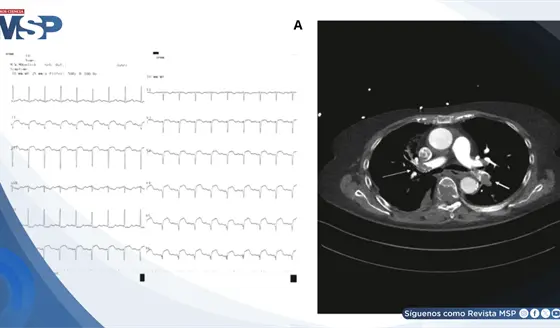

Embolia pulmonar masiva simuló infarto agudo de miocardio en paciente con troponina elevada